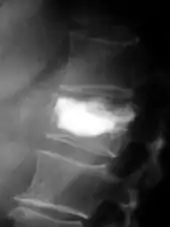

Pour le diagnostic initial, la radio X classique a une importance centrale. L'indication pour des projections sur deux plans est toujours donnée en cas de soupçon de tumeur osseuse[87]. Les métastases ostéolytiques sont caractérisées par une perte de densité osseuse. Ceci se reconnaît sur la radio par un noircissement plus élevé, en raison de la plus grande transparence aux rayons X. Inversement, les métastases ostéocondensantes présentent à cause de la plus grande densité osseuse un noircissement inférieur. Les métastases ostéolytiques sur la colonne vertébrale sont nettement plus difficiles à reconnaître : seulement quand environ 50 % de la densité totale de l'os a disparu[87].

- Comparaison scanner/IRM pour des métastases ostéolytique d'un cancer du sein dans la colonne vertébrale

Scanner sagittal reconstruit, représentation dans la fenêtre osseuse. Comme la patiente avait des métastases dans toutes les régions du corps, elle ne pouvait pas lever les bras pour l'examen, ce pourquoi les mains sont présentées.

Scanner sagittal reconstruit, représentation dans la fenêtre osseuse. Comme la patiente avait des métastases dans toutes les régions du corps, elle ne pouvait pas lever les bras pour l'examen, ce pourquoi les mains sont présentées. Scanner sagittale, parties molles. Outre les métastases dans la colonne vertébrale, qui envahissent en partie le canal médullaire vers l'arrière, métastases aussi dans le sternum. Plus des métastases dans le foie.

Scanner sagittale, parties molles. Outre les métastases dans la colonne vertébrale, qui envahissent en partie le canal médullaire vers l'arrière, métastases aussi dans le sternum. Plus des métastases dans le foie. IRM natif avec pondération T1.

IRM natif avec pondération T1. IRM sagittal natif avec pondération T1. On voit clairement l’extension jusqu'aux lames vertébrales.

IRM sagittal natif avec pondération T1. On voit clairement l’extension jusqu'aux lames vertébrales.